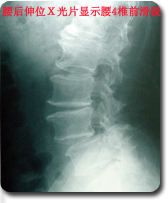

后路内窥镜下(METRx)腰椎管减压,椎间融合,经皮椎弓根螺钉(Sextant)复位内固定术

采用国际领先微创手术技术--后路内窥镜(METRx)行腰椎间盘摘除,椎管减压,并采用经皮椎弓根螺钉系统(Sextant)行复位和内固定。治疗腰椎间盘突出,椎管狭窄以及腰椎不稳等疾病。 优点:本手术采用Sextant系统通过小的皮肤切口直接放置腰椎椎弓根螺钉系统,经皮复位内固定,同时结合腰椎间盘镜(METRx)通过一个小切口(1.8cm)完成腰椎管减压,椎间植骨和融合器植入,本手术方式将Sextant技术与METRx技术相结合,以达到微创腰椎管减压、复位、融合和内固定。